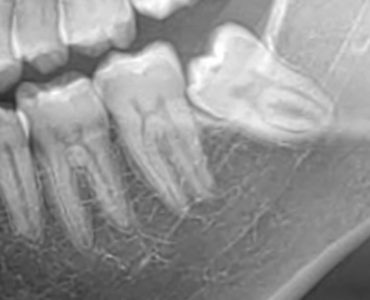

Didascalia foto : L’ortopantomografia (OPT) è l’esame standard per valutare la posizione e l’anatomia del dente del giudizio. In questa immagine si osserva il rapporto di vicinanza tra le radici e il canale mandibolare, punto di partenza per ogni corretta diagnosi.

L’ortopantomografia (OPT) costituisce l’esame di primo livello e consente una valutazione generale della posizione del dente e del suo rapporto con il canale mandibolare. Tuttavia, essendo un esame bidimensionale, può presentare limiti in termini di precisione.

Nei casi in cui si osservi una possibile sovrapposizione tra radici e canale, è indicato un approfondimento mediante CBCT (tomografia computerizzata a fascio conico), che permette una valutazione tridimensionale accurata e una pianificazione terapeutica più sicura.